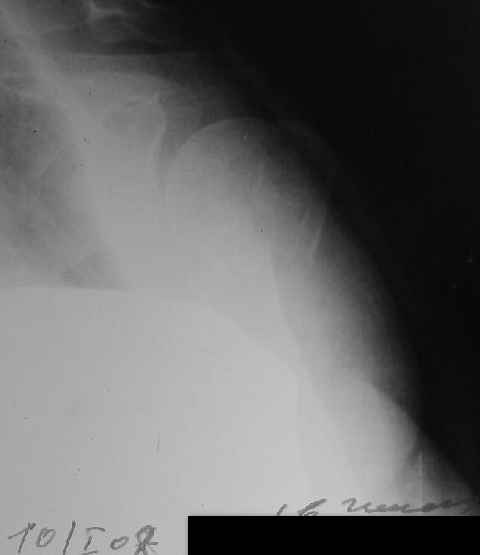

Hello,I am presenting a case of 80 year old male patient right handed known case of hypertension, diabetes and history of CVA 2 years back had a fall in the hosue 10 days back and came to me for pain and ecchymosis around the right shoulder. Xray shows evidence of comminuted fracture proximal humerus extraarticular. He is a doctors father and the doctor wants to know is there any minimally invasive procedure we can do ... I have advised him to go for complete surgery in the form of the AO locking plate under general anesthesia. He is a little reluctant for complete general anaesthesia. My questions to the house is ...1. Is there any other option besides the locking plate ?? (Less invasive) 2. If he is not medically fit for surgery, then can we leave him alone if yes what are the chances of going it into non union? Awaiting your reply Dr Neeraj Bijlani

Fragments now look severely displaced.